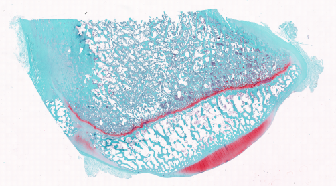

天狼星染色vs股骨病理分析

番红快绿